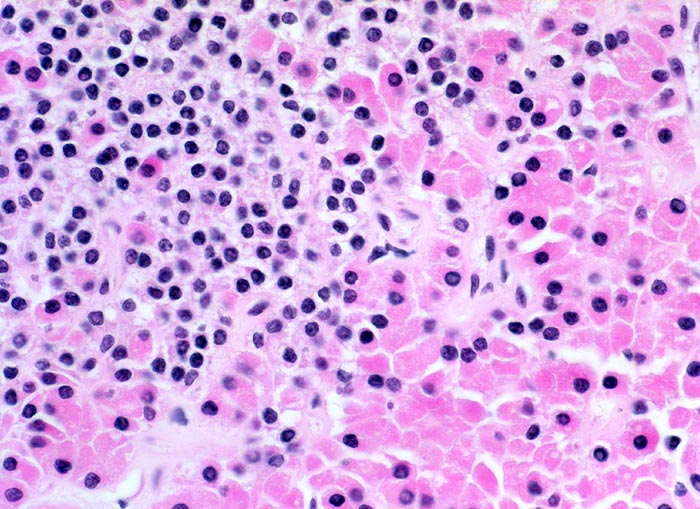

Ausschnitt aus einem hyperplastischen Knoten. Neben aktiven Hauptzellen sind rechts im Bild und zwischen die Hauptzellen eingestreut zahlreiche oxyphile Zellen mit reichlich eosinophilem feinkörnigem Zytoplasma erkennbar.

Der Patient leidet an einer chronischen Niereninsuffizienz. Die glomeruläre Filtrationsrate ist auf 25% reduziert. Unter anderem ist eine Hypokalzämie und eine Hyperphosphatämie vorhanden. Die Serumkonzentration des Parathormons ist erhöht. Die Diagnose eines sekundären Hyperparathyreoidismus wird gestellt.